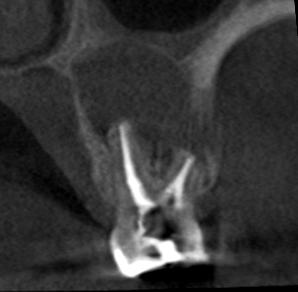

#14 S-RCT (buccal approach for all roots)